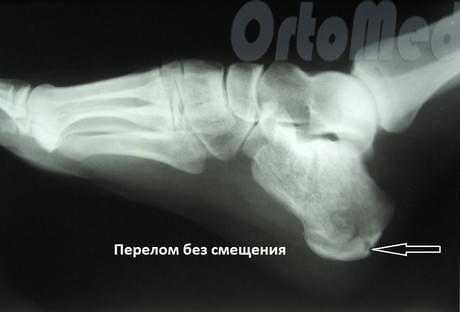

Переломы без смещения

Компрессионные и оскольчатые переломы

Лечение сложных внутрисуставных переломов пяточной кости связано с существенными затруднениями, обусловленными сложностью восстановления нормального взаиморасположения отломков и их удержания до момента сращения. С учетом вида перелома и характера смещения могут применяться следующие методы: